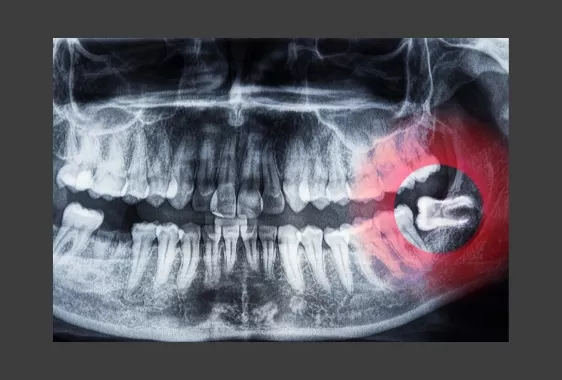

Простой информативный метод определения положения восьмерок – панорамный снимок челюсти. Когда встает вопрос о наличии воспаления, кисты, новообразования, специфического строения корней, назначается дентальная компьютерная томография. Теоретическая информация представлена для ознакомления. Окончательно узнать можно только на консультации в стоматологии. Придя в «Реферта» на осмотр, вы сразу сможете пройти обследования на месте, получить подтверждение и рекомендации по зубам мудрости.